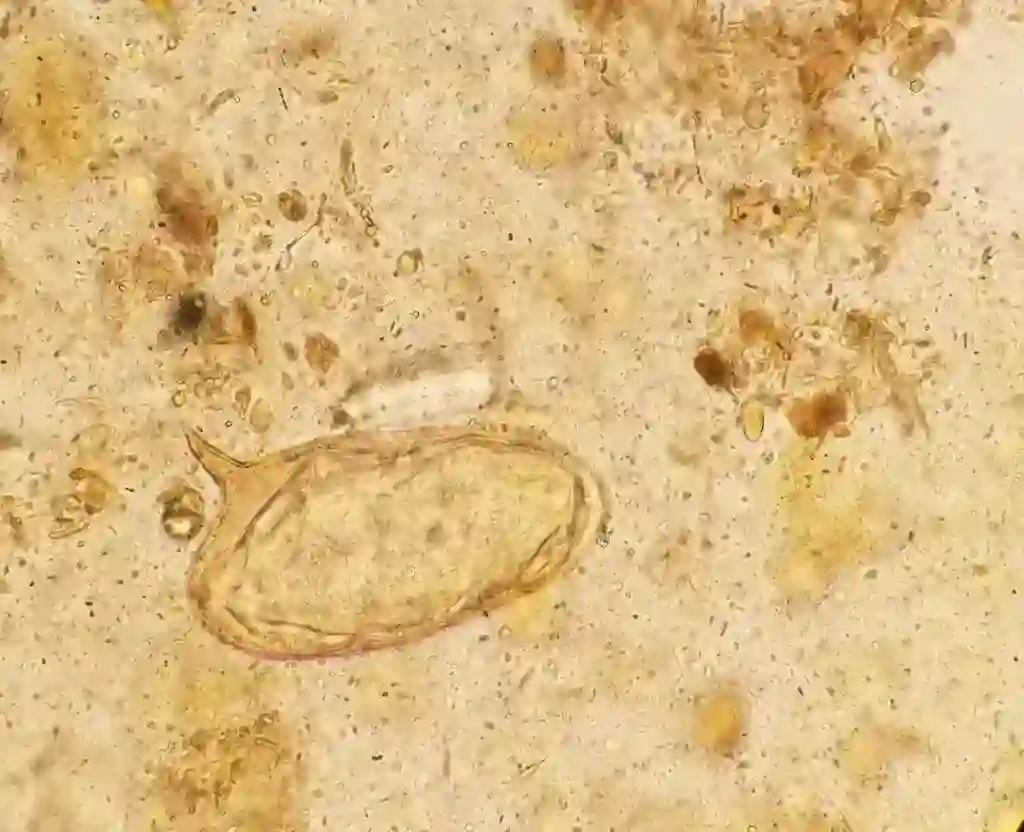

Nanoscopy appraisal of sputum is utilized in remembering Paragonimus westermani eggshells, Strongyloides stercoralis nymphs, Ascaris lumbricoides nymphs and hookworm nymphs. Sputum should be acquired from the lower respiratory passages instead of a sample containing mainly saliva.

This assessment is used to restrict the detection of parasitic infestation. It comprises the amount of matter and examination of specimens for ova and parasites by conventional iodine . This examination will not catch sight of Cryptosporidium or Cyclospora cayetanensis.